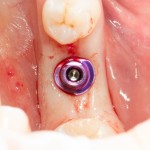

Поэтому, по мере накопления опыта, выяснилось, что не всё тут так однозначно, единственным критерием выбора, с имплантатами или без, является возможность стабилизации импланта в существующем объеме костной ткани. То есть, если после правильной подготовки лунки имплантат удерживается в 1-2 мм костной ткани, то какие могут быть препятствия для установки имплантата одновременно с синуслифтингом?

Вот пример. В нашей клинике мы используем три имплантационные системы компании Dentsply Sirona Implants: XiVE, Ankylos и Astratech. Они существенно различаются по макродизайну. Более того, в отличие от субгингивальных XiVE и Astratech, Ankylos — это субкрестальная система, предполагающая погружение платформы ниже уровня альвеолярного гребня.

Это значит, что использовать имплантаты Ankylos при расстоянии до дна синуса менее 2 мм будет проблематично (но возможно, см. клинический пример). Там, конечно, есть специальные заглушки и всё такое… но, к чему этот геморрой?

Зато в таких условиях отлично стабилизируется XiVE и, внезапно, Nobel Replace, еще внезапнее — Dentium (последние два мы не используем в практике):

Поэтому, если на практике встаёт вопрос о синуслифтинге и имплантации при незначительных (менее 2 мм) расстояниях до дна верхнечелюстного синуса, возможность стабилизации является одним из факторов выбора имплантационной системы для конкретного клинического случая. Учитывайте это, планируя лечение пациента.

решение о проведении имплантации одновременно с синуслифтингом принимается, исходя из возможности стабилизации имплантата в существующем объеме костной ткани. А это, в свою очередь, зависит от макродизайна импланта и хирургического протокола при его установке.